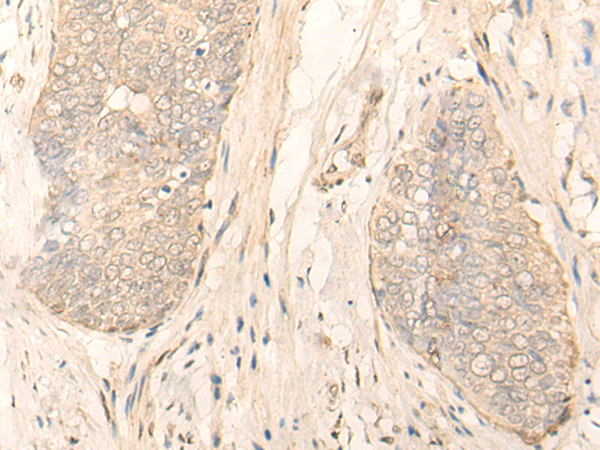

分类: 科研抗体货号: P09634别名: HEL-S-98n应用: WB,IHC反应种属: Human